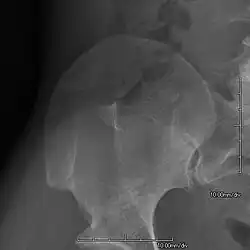

An elbow of a man with nail–patella syndrome (NPS)

This is a view from a different angle of the same man's other elbow